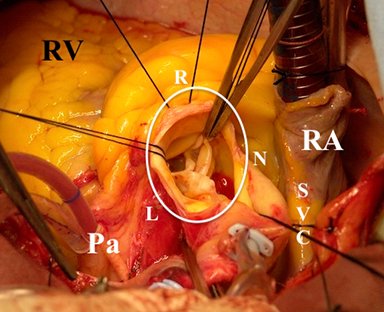

En esta sección se visualizarán cirugías reales en pacientes. Las fotografías por lo tanto

-si bien claras- en ocasiones privilegian la seguridad del paciente antes de

la exposición anatómica ideal.